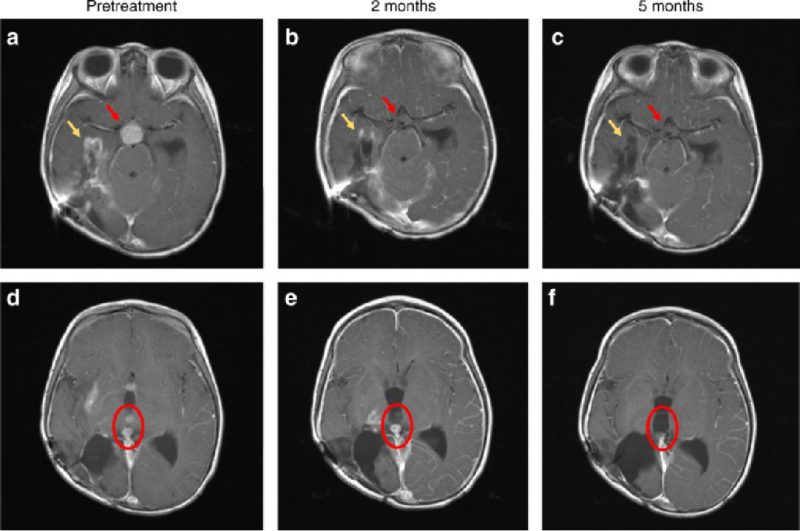

一个3岁的女孩,她在5个月大时被诊断出患有高级神经胶质瘤,在接受了手术和放化疗后,病情持续恶化,临床医生说已经没有更好的治疗办法。但是她的父母不肯放弃,用她的手术组织切片做了全基因组测序,结果显示存在ETV6-NTRK3融合,幸运的是,她入组了larotrectinib(拉罗替尼)的临床试验。仅4周后,她的嗜睡,头痛或呕吐的情况明显好转,饮食良好,说话清晰。6周后,她能够独立行走,可以正常交流,并且精力充沛。到第8周时,她跑步,跳舞并继续学习。下面的CT检查证实了她脑部的病灶已接近完全缓解!

红色箭头:脑部肿瘤治疗2个月后消退,并在5个月后持续缓解;

黄色箭头:2个月时明显改善,5个月时接近完全缓解;

红色圆圈:脑室内病变在2个月后好转,并在5个月后完全消退。